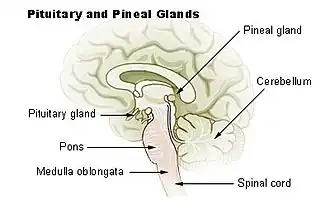

Medulla oblongata (middenonder)

De medulla oblongata[8] of het verlengde merg[9] is het gedeelte van de hersenen dat de hersenstam met het ruggenmerg verbindt. Het is tijdens de embryonale ontwikkeling ontstaan uit het myelencephalon. Men is het er niet over eens of het een onderdeel van de hersenstam is, of op zichzelf staat. Het verlengde merg zendt opdrachten vanuit de hersenen door naar alle lichaamsdelen. Tevens bevat het centra die de hartslag, ademhaling, spijsvertering en bloeddruk reguleren.